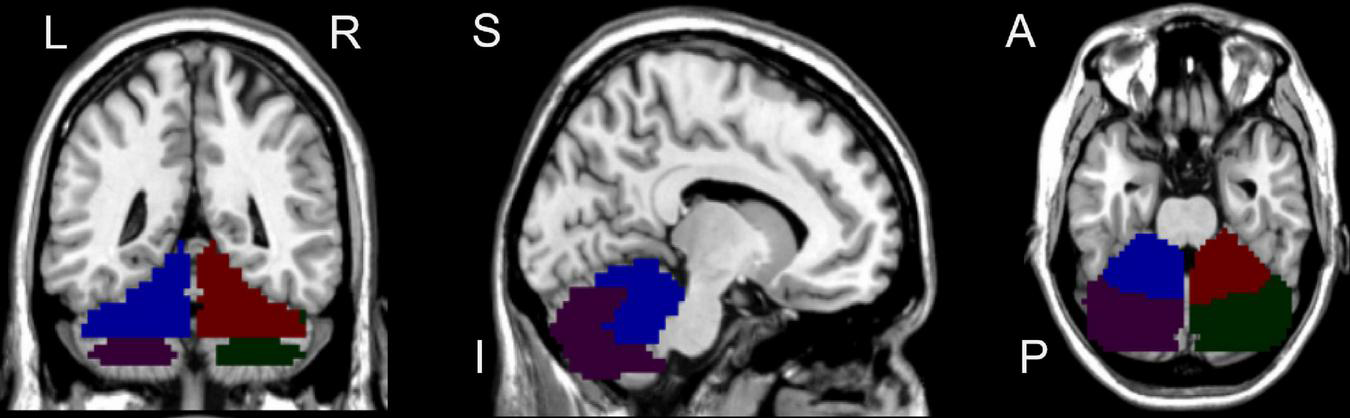

We selected the seed region of interest in the bilateral CAL and CPL (Figure 2) by xjView.4 Then, a voxel-wise FC analysis of each region of interest was performed on the resting-state data for all subjects. First, the blood-oxygen-level-dependent time series of the voxels within each seed region were averaged to obtain the reference time series for the seed region. Second, for each subject and each seed region, a correlation map was obtained by computing the correlation coefficients between the reference time series and the time series of the rest of the whole brain voxels. Finally, the correlation coefficients were converted to z-values using Fisher’s r-to-z transformation to improve the normality (Lowe et al., 1998).

FIGURE 2

Seed regions of interest for functional connectivity. Blue region represents left cerebellum anterior lobe; Purple region represents left cerebellum posterior lobe; Red region represents right cerebellum anterior lobe; Green region represents right cerebellum posterior lobe. L, left; R, right; S, superior; I, inferior; A, anterior; P, posterior.